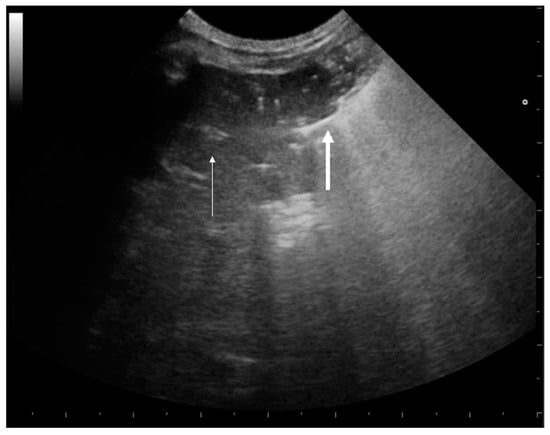

3.1.2. Pleural Effusion

- Lichtenstein, D.A. Lung ultrasound in the critically ill. Ann. Intensive Care 2014, 4, 1. [Google Scholar] [CrossRef] [PubMed]

- Brogi, E.; Gargani, L.; Bignami, E.; Barbariol, F.; Marra, A.; Forfori, F.; Vetrugno, L. Thoracic ultrasound for pleural effusion in the intensive care unit: A narrative review from diagnosis to treatment. Crit. Care 2017, 21, 325. [Google Scholar] [CrossRef] [PubMed]

- Chichra, A.; Makaryus, M.; Chaudhri, P.; Narasimhan, M. Ultrasound for the Pulmonary Consultant. Clin. Med. Insights Circ. Respir. Pulm. Med. 2016, 10, 1–9. [Google Scholar] [CrossRef]

- Dietrich, C.F.; Mathis, G.; Cui, X.W.; Ignee, A.; Hocke, M.; Hirche, T.O. Ultrasound of the pleurae and lungs. Ultrasound Med. Biol. 2015, 41, 351–365. [Google Scholar] [CrossRef]

- Han, J.; Xiang, H.; Ridley, W.E.; Ridley, L.J. Jellyfish sign: Pleural effusion. J. Med. Imaging Radiat. Oncol. 2018, 62 (Suppl. S1), 33. [Google Scholar] [CrossRef] [PubMed]